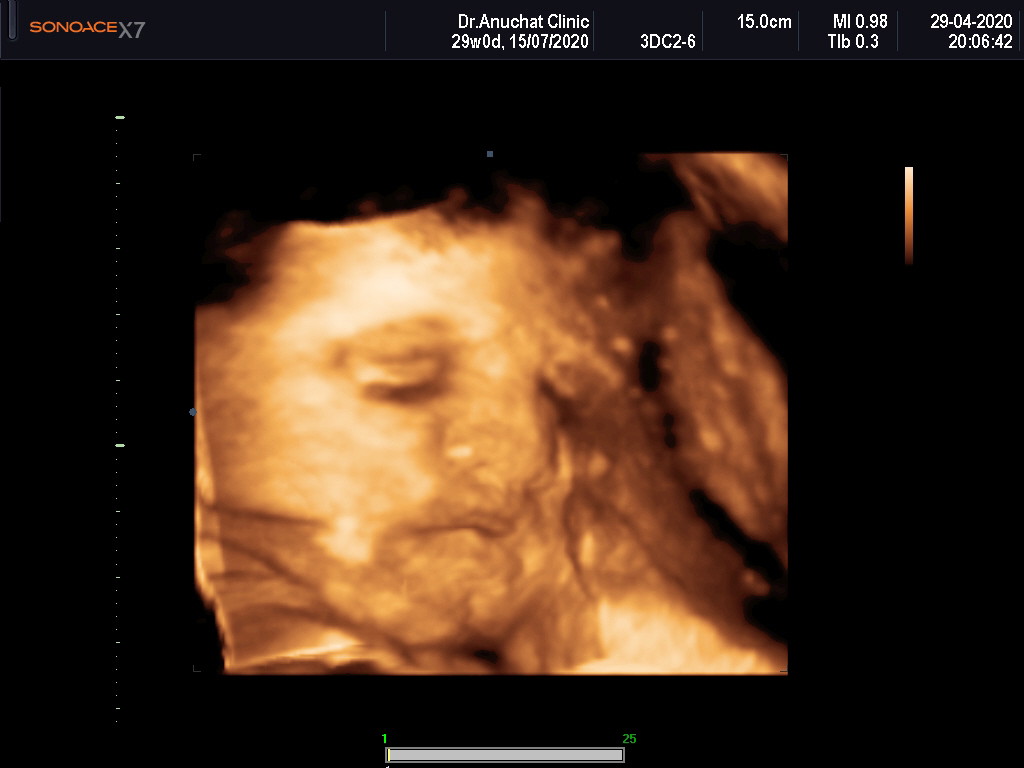

สงสัยคงหิวดูดนิ้วซะงั่น🤣🤣

เอามือบังเหมือนกันค่ะ😆😆